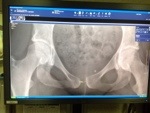

Lately I have been reading medical journal articles about women with extreme cases of Diastasis Symphysis Pubis (separated pelvis) during childbirth. In two of those cases the women were considered healed with gaps still larger than mine is today.

He’s actually going to remove my symphysial disk — the cartilage between the two halves of my pubis. Then he will clamp the bones together while he secures the plate into place. Removing the symphysial disk, he explained, would cause scar tissue to fill the gap. Scar tissue and cartilage are very similar so it will do the same job and my pelvis will be stable again.